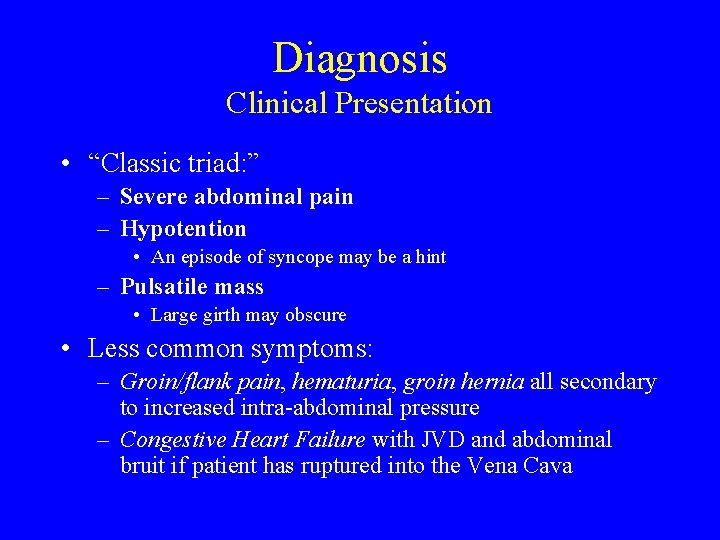

Diagnosis Clinical Presentation • “Classic triad: ” – Severe abdominal pain – Hypotention • An episode of syncope may be a hint – Pulsatile mass • Large girth may obscure • Less common symptoms: – Groin/flank pain, hematuria, groin hernia all secondary to increased intra-abdominal pressure – Congestive Heart Failure with JVD and abdominal bruit if patient has ruptured into the Vena Cava

Diagnosis Clinical Presentation – RAAA is misdiagnosed 16% - 30% of the time • Common misdiagnosis: – Renal colic, perforated viscous, diverticulitis, gastrointestinal hemorrhage and ischemic bowel – Mortality rates for correctly diagnosed was 58%, and 44% for misdiagnosed • Likely due to fact that less severe ruptures have a more subtle presentation and can survive longer before going to OR